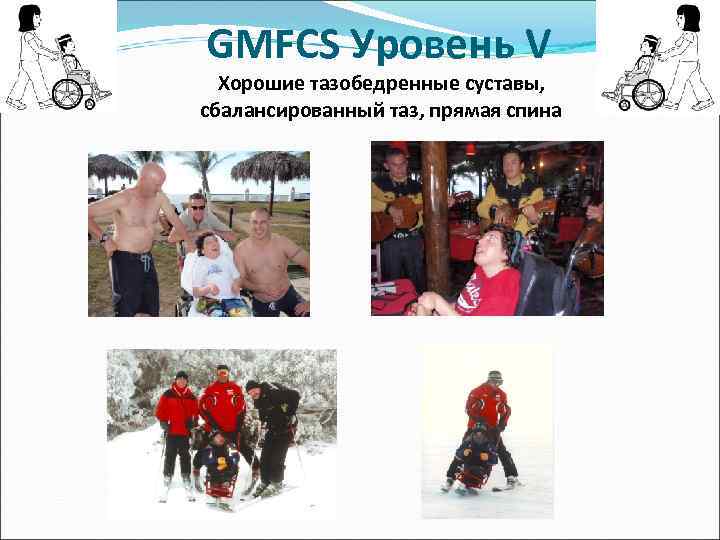

GMFCS Уровень V Цель лечения: -Хорошие тазобедренные суставы -сбалансированный таз -ровная спина

GMFCS Уровень V Цель лечения: -Хорошие тазобедренные суставы -сбалансированный таз -ровная спина

GMFCS Уровень V Хорошие тазобедренные суставы, сбалансированный таз, прямая спина